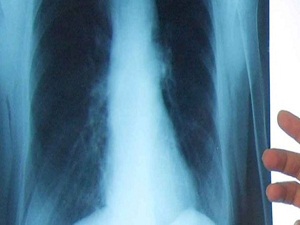

Akciğer kanseri her yıl milyonlarca ölüme neden oluyor

Akciğer kanserinden dünyada her yıl yaklaşık 1.4 milyon kişinin hayatını kaybettiği öğrenildi.

Dünyada her yıl 1.6 milyon yeni akciğer kanseri teşhis edildiğine dikkati çeken Yılmaz, "Her yıl 1.4 milyon kişi akciğer kanseri nedeniyle hayatını kaybetmektedir ve Türkiye'de de 30 bin yeni akciğer kanseri tanısı konulmaktadır" bilgisini verdi.

Akciğer kanserinin, kanserden ölümler sıralamasında Dünya'da ve Türkiye'de ilk sıralarda yer aldığına dikkati çeken Yılmaz, şunları kaydetti: